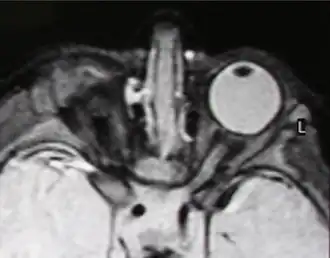

Правосторонняя анофтальмия (МРТ-изображение)